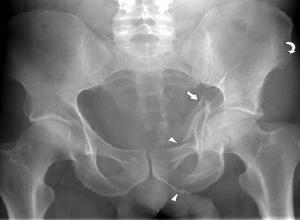

髋臼骨折大多数是由股骨头受到外界暴力传导引起的,常会遗留以下三种并发症:

1、异位骨化

异位骨化是髋臼骨折患者最主要的并发症,是导致手术治疗预后不良的主要原因,有1/3的患者需要再次手术治疗才能解除。异位骨化发生的原因与损伤严重程度、手术位置、骨膜剥离程度、截骨术的应用等因素有关。

2、坐骨神经损伤

坐骨神经损伤可发生于髋臼骨折受伤当时,发生率为16%~33%,也可以发生于外科治疗时,发生率约为17.4%。

3、创伤后关节炎

创伤后关节炎是髋臼骨折的远期并发症,多见于髋臼上臂骨折和髋关节后脱位。其发生原因与股骨头承重面骨折、永久性关节半脱位、关节面不对称等因素有关,手术治疗时尽量恢复良好的解剖复位,尤其是髋臼负重面的解剖复位可以有效的降低创伤后关节炎的发生率。